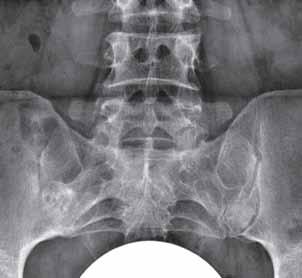

Rycina 2.11.

Geody podchrzęstne powierzchni stawowych stawów IP 1 i MTP 1 od stron przyśrodkowych (oznaczone kolorem żółtym). Płytka nadżerka brzeżna przyśrodkowej powierzchni głowy paliczka bliższego palca 1 P (oznaczona kolorem czerwonym).